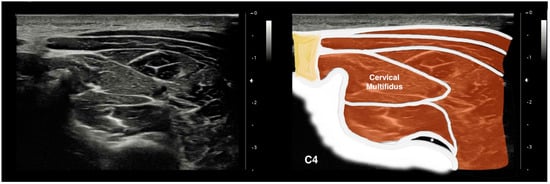

2.4.1. Cervical Multifidus and Longus Colli Imaging Acquisition